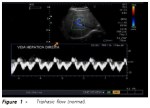

Στον έλεγχο της ροής της ηπατικής φλέβας ελέγχθηκε διαφορετική κυματομορφή ( to and fro)

από την φυσιολογική (triphasic).